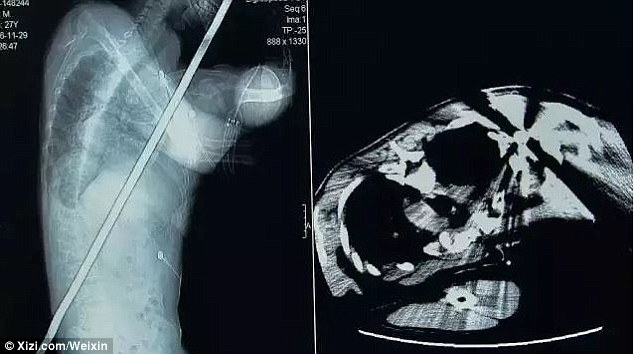

Imbasan X-ray dilakukan ke atas A Feng dan mendapati rod besi itu telah mengenai beberapa organ dalamannya seperti perut, paru-paru, hati dan buah pinggangnya.